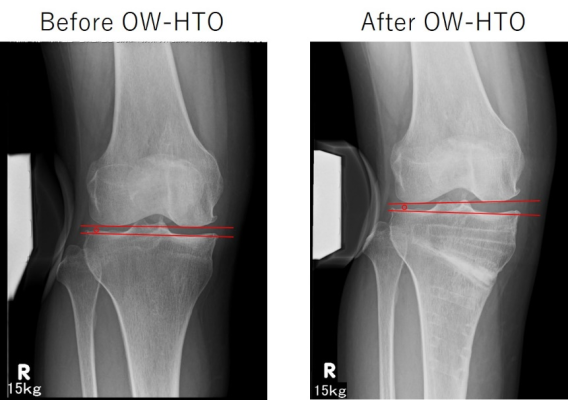

内側開大式高位脛骨骨切り術(OW-HTO)では、MCL浅層の解離が必須です。MCL解離直後は内側が緩むが、骨切り部開大後は術前と同等になるとの報告がある一方、内側がややタイトになるという報告もあり、術前後における内側laxityの変化を定量的に検討した報告は限られていました。本研究では、OW-HTO前後における内側laxityの変化について定量的に検証し、その影響因子や臨床成績との関連などを調査しました。術前とOW-HTO後1年時の外反ストレス(15㎏)膝正面XpにおけるJLCAや関節裂隙幅などを計測しました。結果は、12例/40例(30%)において、内側関節裂隙の開大を伴う1度以上のJLCAの変化(内側の緩み)を術後に認めました(図A)。術前後の内側laxityの変化(ΔJLCA)に有意に相関を認めた因子は、骨切り高位(Distance AとB)であり、ΔJLCA > 1°のカットオフ値はDistance Aで35mm、Distance Bで39mmであった。一方、ΔJLCAは術後1年のKOOSとの有意な関連は認めず、臨床的意義に関しては今後の課題です。関節面に近い骨切りでは、MCLの解離もより近位となることが術後の内側の緩みの原因となったかもしれないと結論付けました(Soejima Y, Akasaki Y, et al. KSSTA 2021)。

図A